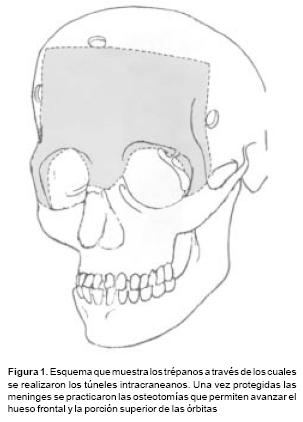

Las osteotomías a utilizar se diseñan previamente en las reconstrucciones tridimensionales obtenidas con la T.A.C., y ésta varía de acuerdo a la deformidad de cada paciente. Las más utilizadas son: osteotomías fronto–orbitarias bilaterales (Figura 1), osteotomía tipo monobloque (Figura 2) y osteotomía fronto–orbito–malar unilateral (Figura 3). La osteotomía seleccionada se dibuja sobre la estructura esquelética disecada utilizando violeta de genciana. En este momento se selecciona 2 o 3 sitios sobre el hueso frontal para las craneotomías. Y una vez completadas estás, se realiza una disección intracraneana muy limitada que sigue las líneas de las osteotomías en el área frontal y orbitaria, creando una serie de túneles intracraneanos y preservando la mayoría de los puentes vasculares entre las meninges y el hueso frontal. El mismo procedimiento se utiliza para el techo orbitario. A través de los túneles se introducen tiras de gasas y separadores muy finos que permiten la realización de las osteotomías con sierras oscilatorias, sin daño a las estructuras subyacentes. Con un endoscopio rígido de visión directa se verifica la hemostasia y la integridad de las meninges luego de realizar las osteotomías. Así mismo bajo visión endoscópica se realiza una cuidadosa disección del área de la Crista Galli y de las alas menores del esfenoides en su unión con la órbita y el frontal, lo que permite completar las osteotomías a nivel central y lateral y la movilización de toda la estructura ósea a avanzar. En los casos de monobloque, la línea de osteotomía se continúa de la pared lateral orbitaria a la unión pterigomaxilar y sobre el piso y la pared medial de la órbita. En estos casos la disyunción con pinzas de Rowe del área pterigomaxilar, se hace necesario a fin de avanzar en un verdadero monobloque el maxilar unido a las órbitas y al hueso frontal (Figura 2).

El cráneo y las órbitas se exponen a través de una incisión bicoronal. El colgajo frontal se eleva en un plano supraperióstico hasta aproximadamente un centímetro por encima del reborde supraorbitario. Entonces el periostio se incide horizontalmente de una cresta temporal a la contralateral. Desde este nivel la disección se continúa subperióstica exponiendo los rebordes supraorbitarios y la emergencia del nervio supraorbitario. El nervio se libera de su orificio de salida con un osteótomo de 2 mm. y la disección subperióstica se continúa por el techo de la órbita, la pared lateral y medial, por detrás de la cresta lacrimal e incluyendo el piso orbitario. Cuando es necesario ésta se puede extender al área cigomática–malar y la región anterior del maxilar. Es fundamental preservar la inserción del músculo temporal, por lo que en la fosa temporal sólo se diseca un túnel un centímetro de ancho que permita introducir separadores y exponer la pared lateral de órbita para la osteotomía. En todo momento se realizó hemostasia cuidadosa con cera de hueso para las perforantes óseas y con el electrocauterio para el resto de los vasos.